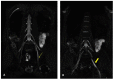

In the present study, through a case series, we highlighted the role of magnetic resonance (MR) in the identification and diagnosis of peripheral neuropathies. MR neurography allows the evaluation of the course of nerves through 2D and 3D STIR sequences with an isotropic voxel, whereas the relationship between nerves, vessels, osteo-ligamentous and muscular structures can be appraised with T1 sequences. Currently, DTI and tractography are mainly used for experimental purposes. MR neurography can be useful in detecting subtle nerve alterations, even before the onset of symptoms. However, despite being sensitive, MR neurography is not specific in detecting nerve injury and requires careful interpretation. For this reason, MR information should always be supported by instrumental clinical tests.